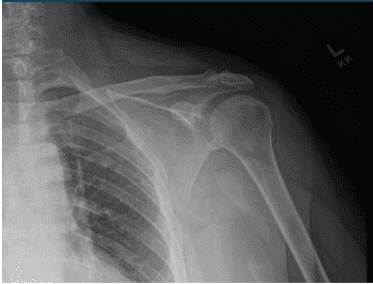

Left Shoulder X-ray

Left shoulder X Ray were presented and discussed and showed normal left shoulder radiographs. Recommended patient to undergo MRI to see the reason behind the pain. Found that there is very minimal AC joint osteoarthritis. No subacromial enthesophyte is visualized. Also noticed, mild rotator cuff tendinosis.